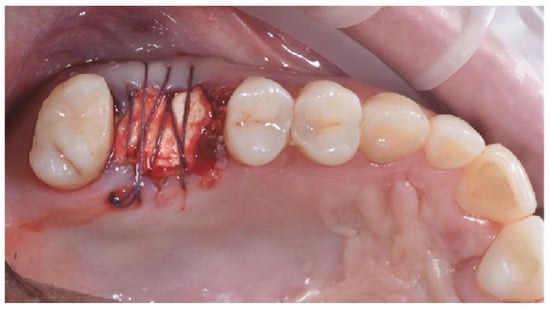

2.5. GBR Procedure

2.6. Outcome Measures